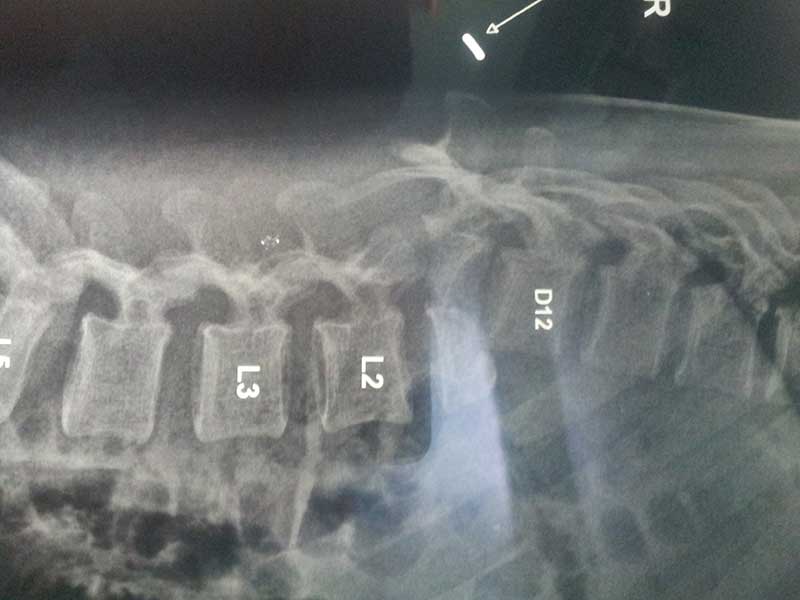

pre op xray 1

Spine Fixation Lumbar Spine

• Spine Fixation Lumbar Spine

PRE OP MRI SPINE INJURY